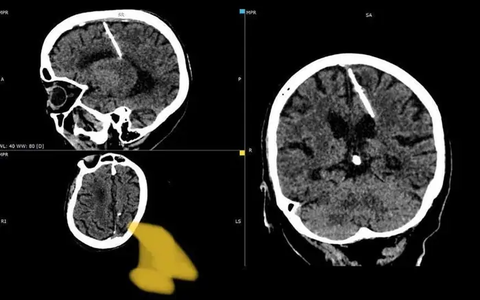

Ca phẫu thuật ngắt hoạt động một bên não kéo dài suốt 10 giờ - Ảnh minh họa

Theo Đài CNN, cuộc phẫu thuật do đội ngũ bác sĩ tại Trung tâm y tế Đại học Loma Linda, bang California (Mỹ) thực hiện trong 10 giờ của ngày 28-9. Sau đó cô bé Brianna Bodley, 6 tuổi, sẽ sống phần đời còn lại chỉ với một bên não còn hoạt động.

Trong lần khám đầu tiên vào tháng 8-2022, các bác sĩ chẩn đoán bé mắc bệnh động kinh nặng. Đến khi cô bé phải nhập viện điều trị một tháng sau đó, họ mới phát hiện bệnh nhân nhỏ tuổi này đang phải vật lộn với một chứng bệnh hiếm gặp tên là viêm não Rasmussen.

Tiến sĩ Aaron Robison, bác sĩ giải phẫu thần kinh nhi khoa tại Loma Linda, sau đó đã đề xuất phẫu thuật “tắt” một bên não của bé gái. Ông lo ngại tình trạng động kinh sẽ khiến não bộ của bệnh nhi tổn thương ngày càng nghiêm trọng.

Việc “tắt” (ngắt kết nối) một trong hai bán cầu não sẽ giúp bán cầu bị bệnh không gây ảnh hưởng đến bán cầu khỏe mạnh, chấm dứt hoàn toàn những cơn động kinh.

Ông Robison cho biết trường hợp của bệnh nhi Brianna chỉ cần ngắt kết nối não là đủ. Não trái của cô bé sẽ tìm cách bù đắp chức năng của phần não phải.